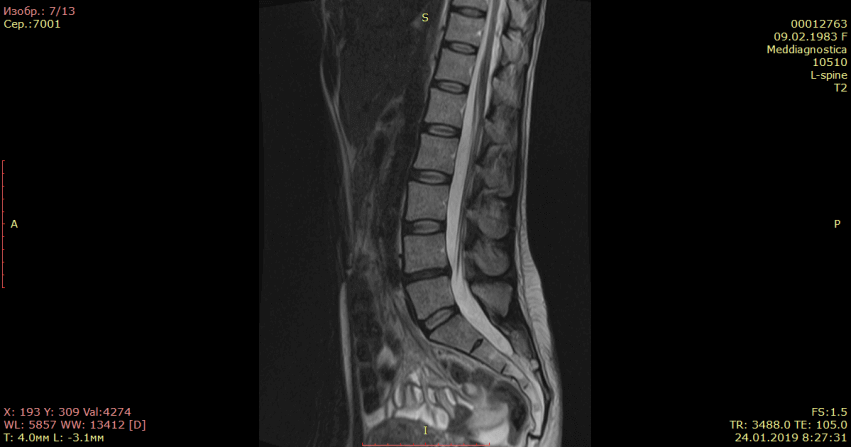

Контрольная МРТ, проведенная через 5 месяцев показала полное отсутствие грыжи диска (см. снимки Ирины ниже):

Обратите внимание на даты проведения МРТ в правом нижнем углу. МРТ исследования проведены на одном аппарате 1.5 теслы в клинике «Меддиагностика» в процессе лечения Ирины. МРТ позвоночника позволяет отследить динамику уменьшения грыжи диска.. Ирина прошла не только курс лечения, но и курс реабилитации